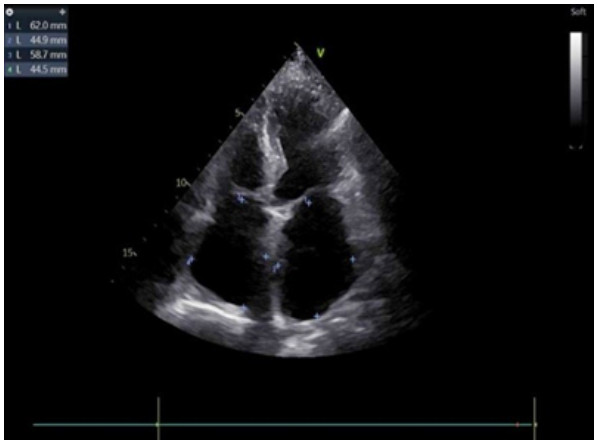

辅助检查:常规心电图示心房颤动。床旁经胸超声心动图示:原左房血栓影未显示(见图 3)。

| 注:左房内团块样回声影未见显示 图 3 患者本次入院当天常规经胸腔超声心动图 |